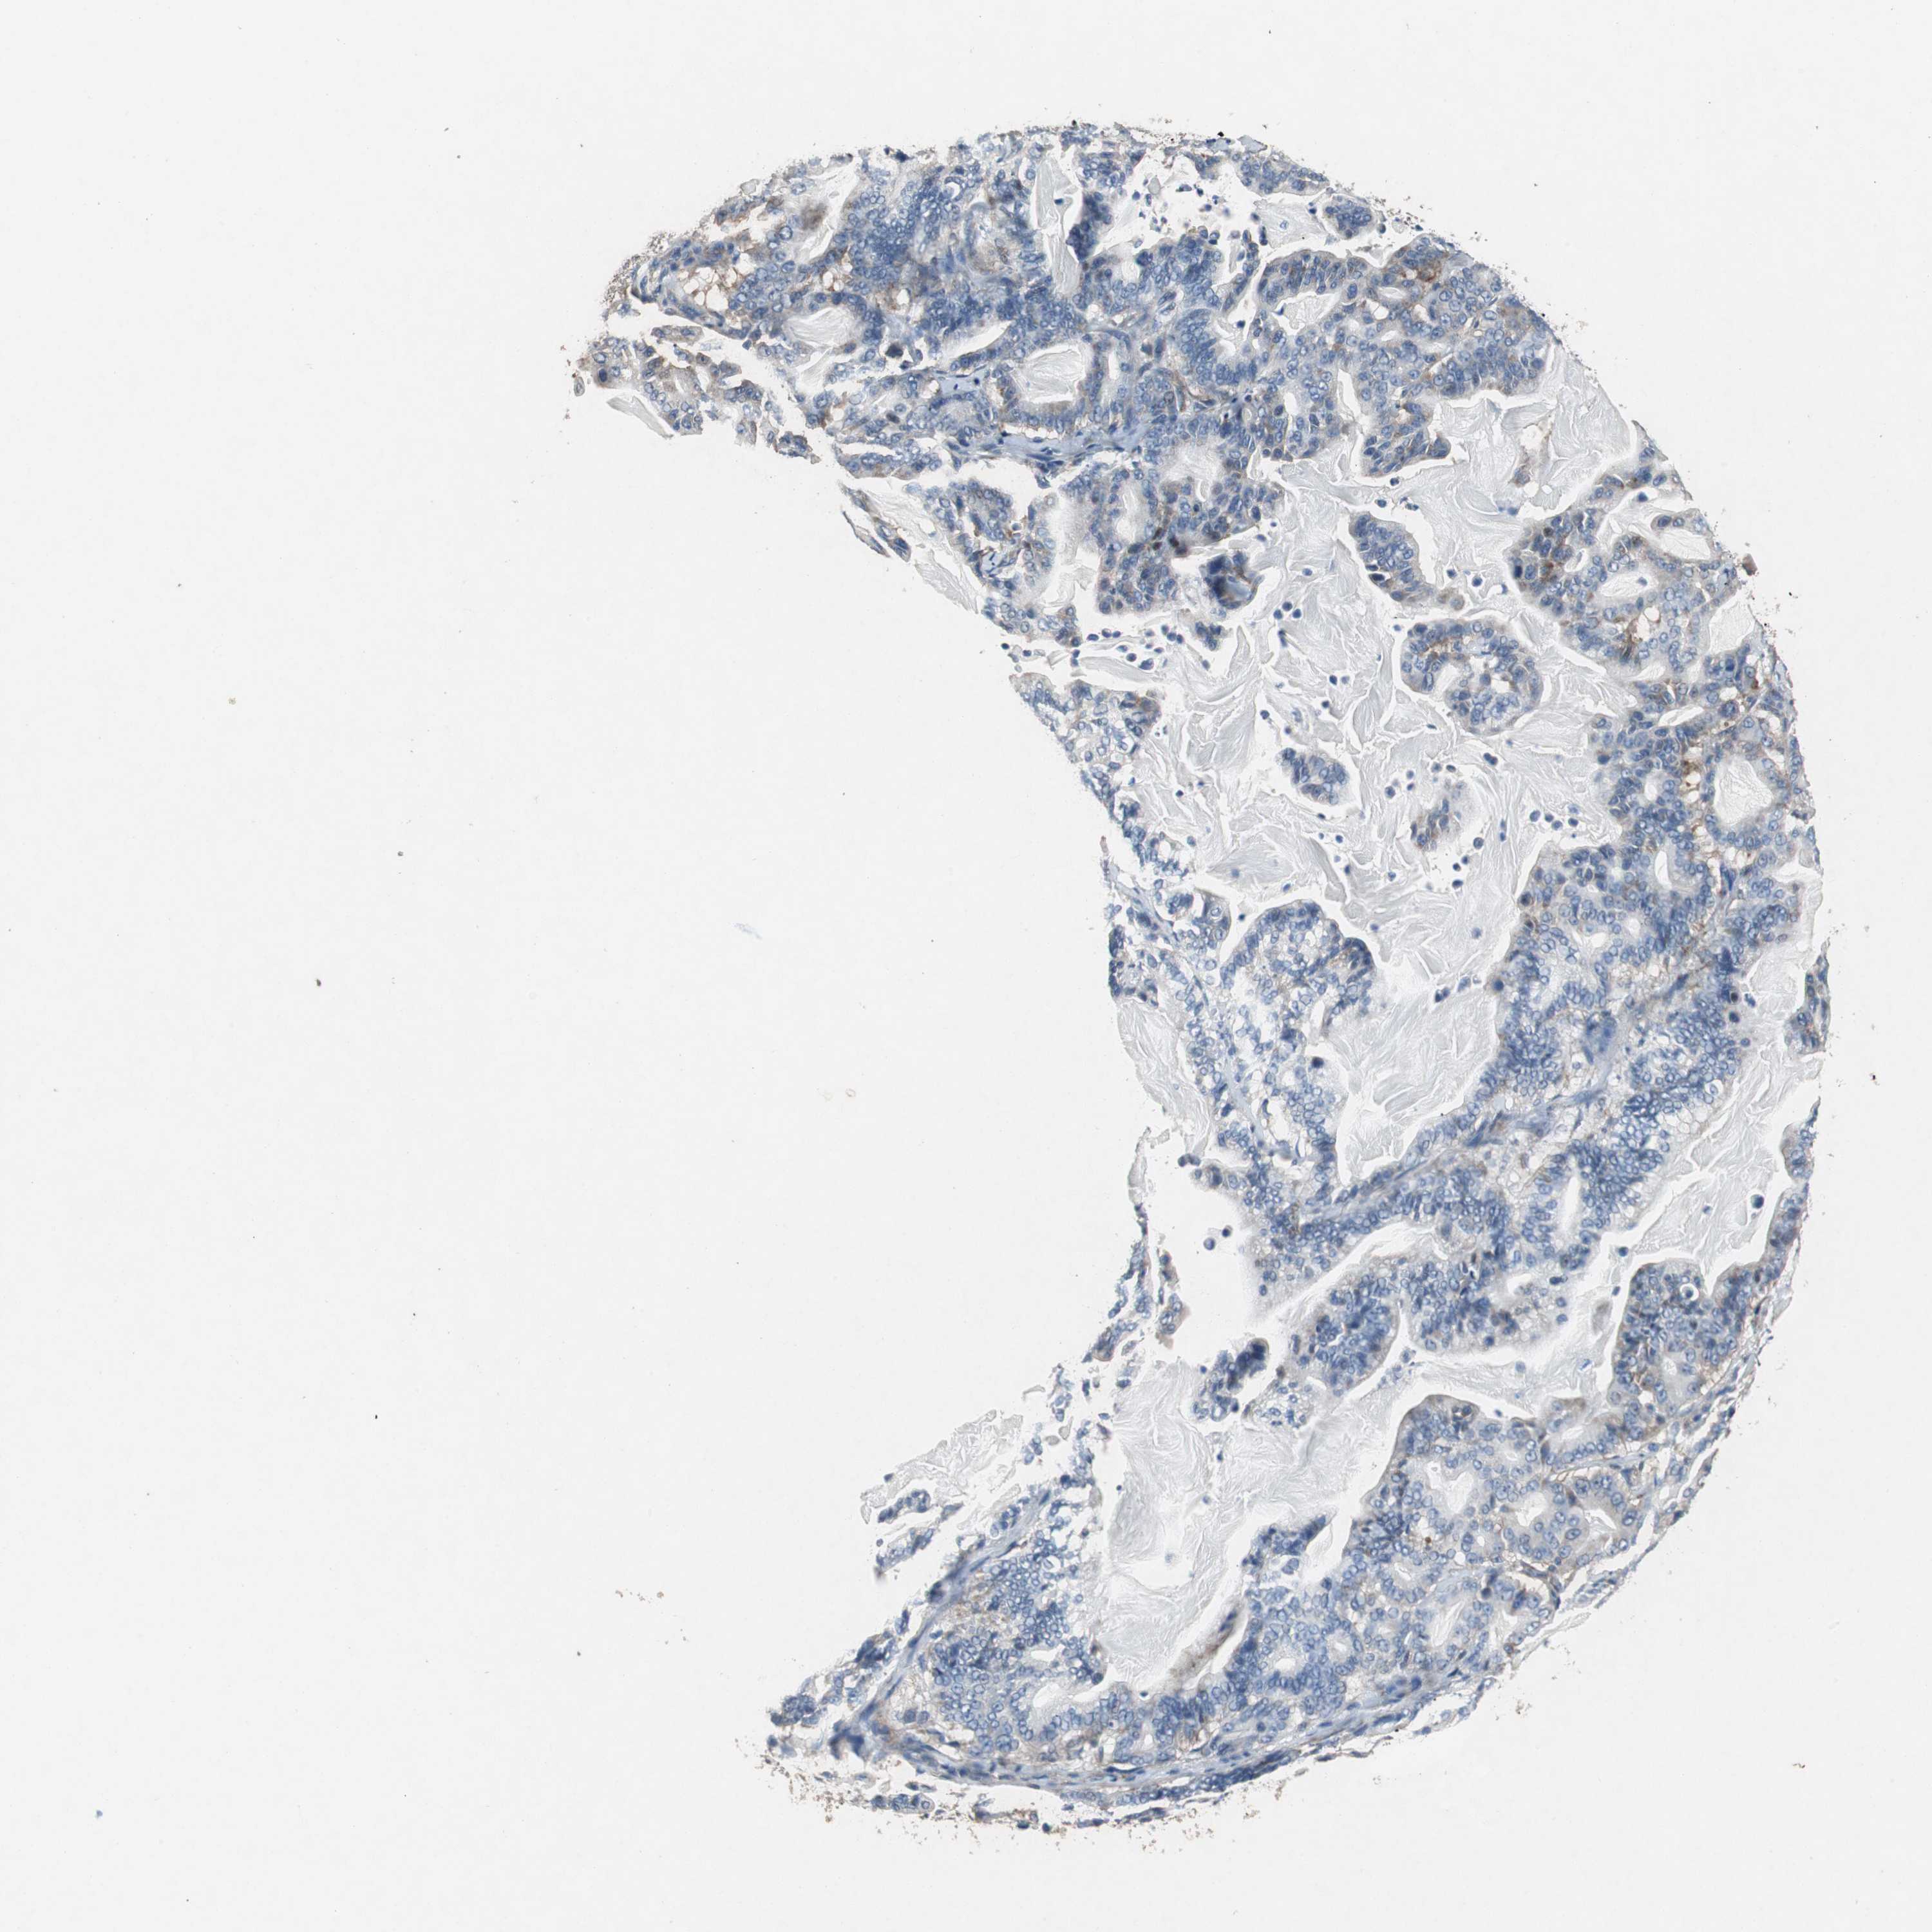

PANCREATIC CANCER - Protein expressioni

A mouse-over function shows sample information and annotation data. Click on an image to view it in a full screen mode. Samples can be filtered based on level of antibody staining by selecting one or several of the following categories: high, medium, low and not detected. The assay and annotation is described here.

Note that samples used for immunohistochemistry by the Human Protein Atlas do not correspond to samples in the TCGA dataset.

Antibody stainingi

Antibody staining in the annotated cell types in the current human tissue is reported as not detected, low, medium, or high, based on conventional immunohistochemistry profiling in selected tissues. This score is based on the combination of the staining intensity and fraction of stained cells.

Each image is clickable and will lead to virtual microscopy that enables deeper exploration of all samples and also displays staining intensity scores, fraction scores and subcellular localization as well as patient and tissue information for each sample.

Antibody HPA006047

Staining

High

Medium

Low

Not detected

Intensity

Strong

Moderate

Weak

Negative

Quantity

>75%

75%-25%

<25%

None

Location

Nuclear

Cytoplasmic/membranous

Cytoplasmic/membranous,nuclear

Adenocarcinoma, NOS

Adenocarcinoma, metastatic, NOS